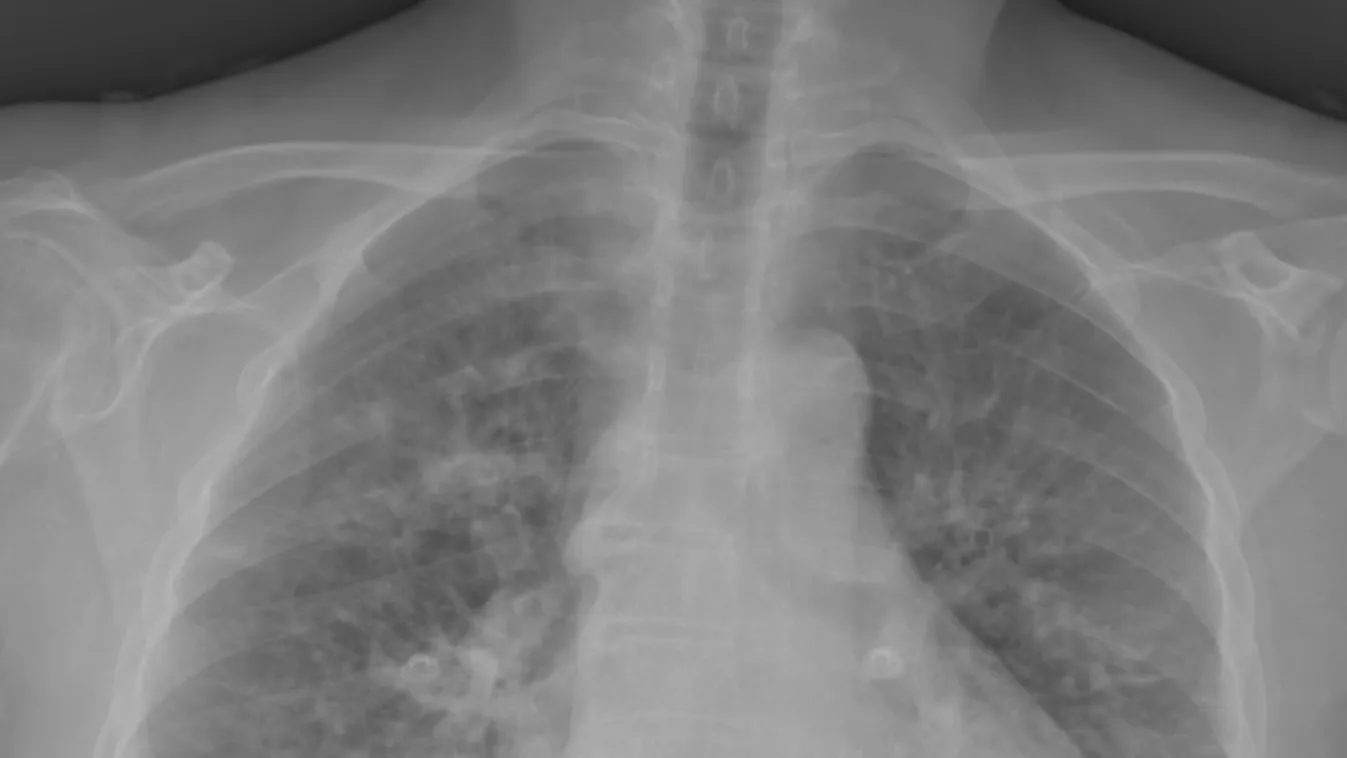

INSIDER 2021. 04. 19. Poszt-Covid lépésről lépésre: így ismerd fel és kezeld a rejtélyes betegséget! A vírusfertőzésen átesett emberek 10-20%-át is érinti a poszt-Covidként is emlegetett összetett tünetegyüttes, és a betegség kezelése feladja a leckét az orvosoknak is.

INSIDER 2021. 04. 14. Ijesztő adat: A koronavírusosok negyede szenved poszt-Covid tünetektől Mára sajnos világossá vált, nemcsak a koronavírus-járvánnyal, hanem a betegség szövődményeivel és utóhatásával is meg kell küzdeni. Az új betegség neve poszt-Covid, aminek gyógyításához több szakterület összefogására lesz szükség.